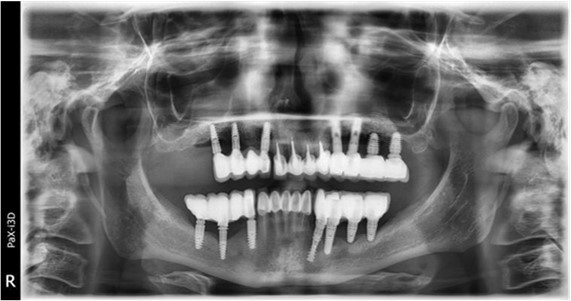

June 2022: Patient presented to our clinic for immediate-loading implant treatment At the time of presentation in 06. 2022, radiologically, advanced peri- implantitis is observed around the implants, with loss of native bone in the affected distal areas (Figure 1)

Figure 1.Panoramic overview picture before rehabilitation 06.2022